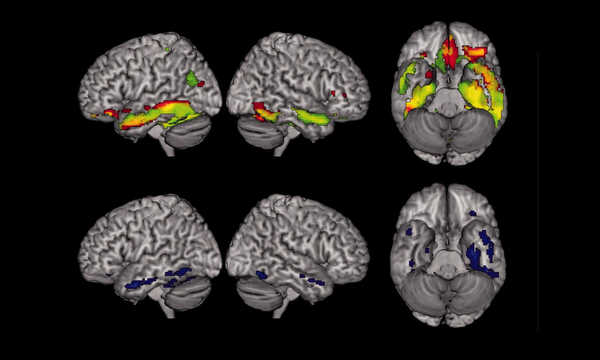

Badanie czynnościowe mózgu MR pozwala ocenić aktywność różnych obszarów mózgu podczas wykonywania określonych zadań

fMRI pozwala określić, które obszary mózgu odpowiadają za mowę, pamięć czy ruch

Funkcjonalny rezonans magnetyczny mózgu umożliwia analizę zmian przepływu krwi związanych z pracą neuronów

Badanie czynnościowe MR stosuje się m.in. w diagnostyce chorób neurologicznych oraz planowaniu leczenia operacyjnego

W aspekcie klinicznym fMRI używany jest np. do precyzyjnej oceny miejsc w korze mózgu, odpowiedzialnych za takie fundamentalne funkcje układu nerwowego jak czucie, ruchy, mowa czy bardziej złożone czynności, jak np. planowanie. Pozwala to na prawidłowe zaaranżowanie ewentualnych operacji z ominięciem miejsc krytycznych, szczególnie istotnych z neurologicznego punktu widzenia.